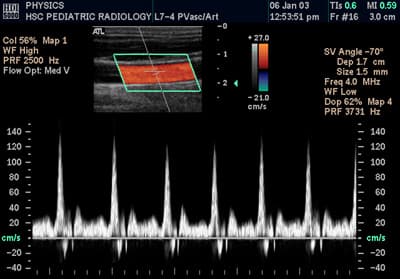

Doppler ultrasonography is medical ultrasonography that employs the Doppler effect to perform imaging of the movement of tissues and body fluids (usually blood), and their relative velocity to the probe. By calculating the frequency shift of a particular sample volume, for example, flow in an artery or a jet of blood flow over a heart valve, its speed and direction can be determined and visualized. Duplex ultrasonography sometimes refers to Doppler ultrasonography or spectral Doppler ultrasonography. Doppler ultrasonography consists of two components: brightness mode (B-mode) showing anatomy of the organs, and Doppler mode (showing blood flow) superimposed on the B-mode. Meanwhile, spectral Doppler ultrasonography consists of three components: B-mode, Doppler mode, and spectral waveform displayed at the lower half of the image. Therefore, "duplex ultrasonography" is a misnomer for spectral Doppler ultrasonography, and more exact name should be "triplex ultrasonography". This is particularly useful in cardiovascular studies (sonography of the vascular system and heart) and essential in many areas such as determining reverse blood flow in the liver vasculature in portal hypertension. Colour Doppler shows the direction of the blood flow in red or blue (either towards or away from the transducer). Meanwhile, spectral Doppler not only shows the direction of blood flow, it also shows the phases (pulsatility) and acceleration of the blood flow. Any sudden changes in direction of blood flow produces audible sounds on the ultrasound machine. In spectral Doppler, the y-axis shows the direction and velocity of the flow. Meanwhile, the x-axis (as known as "baseline") shows the flow over time. The gradient at any point on the waveform would therefore shows the acceleration of the flow. In "antegrade" flow, the blood flows according to the normal flow within the circulatory system (e.g. veins flow towards the heart while arteries flows away from the heart). In "retrograde" flow, the flow would reverse (e.g.